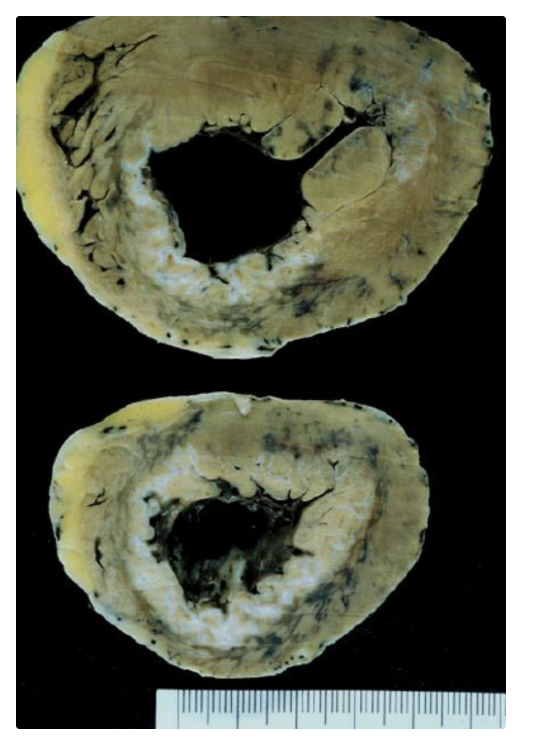

Fibroelastoma papilar